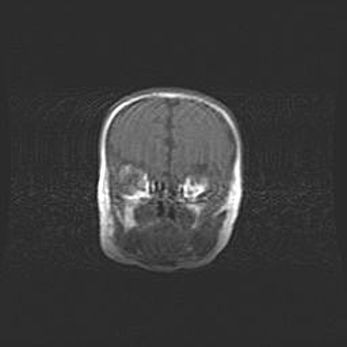

Открытая гидроцефалия.

Возраст: 6 месяцев 15 дней

Вес: 6200 г

Пол: женский

Окружность головы: 41 см

Срок гестации: 38 недель

Гидроцефалия головного мозга у новорожденных – это скопление избыточного количества цереброспинальной жидкости в головном мозге. Ее избыточное скопление в мозге приводит к патологическому расширению желудочков мозга (четырех полостей, расположенных в глубине белого вещества мозга, заполненных цереброспинальной жидкостью и связанных узкими проходами).

Открытый тип гидроцефалии (сообщающаяся) наблюдается тогда, когда нарушен механизм всасывания ликвора в системный кровоток. При этом типе причиной заболевания чаще всего является перенесенные ранее инфекции (например: менингит),  либо же наличие крови в субарахноидальном пространстве.